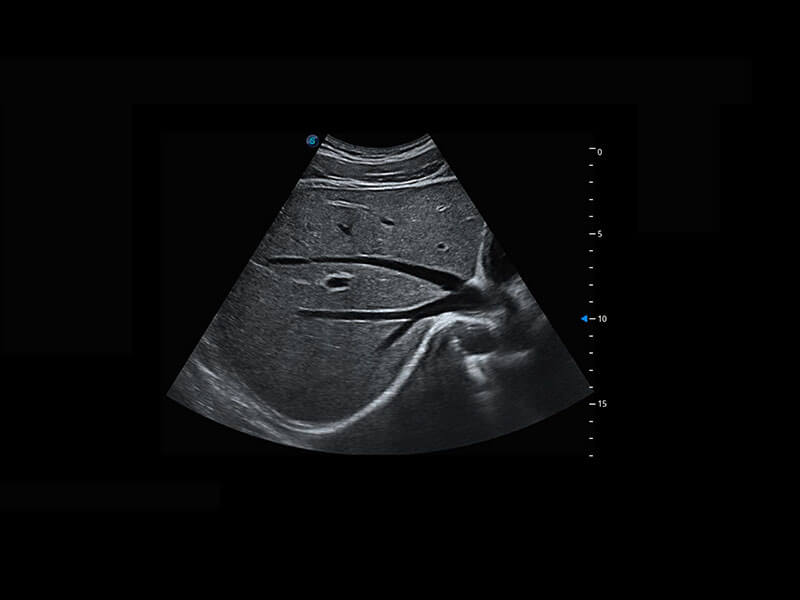

P60提供简单易学易用的高端诊断工具,为您中晚孕筛查提供快速清晰的解剖信息。

1 OFD(HC): 87.03 mm

HC: 251.00 mm

GA: 27w 1d

HC/AC: 96.13 %

2 BPD: 70.56 mm

GA: 28 w 2d

S-Fetus(acq.)

&

S-Fetus(meas.)

S-Fetus能够助您在实时扫查过程中自动识别标准切面、自动测量并录入报告。一个按键,即可快速、高效地获取胎儿生理指标,简化您的产科检查操作。